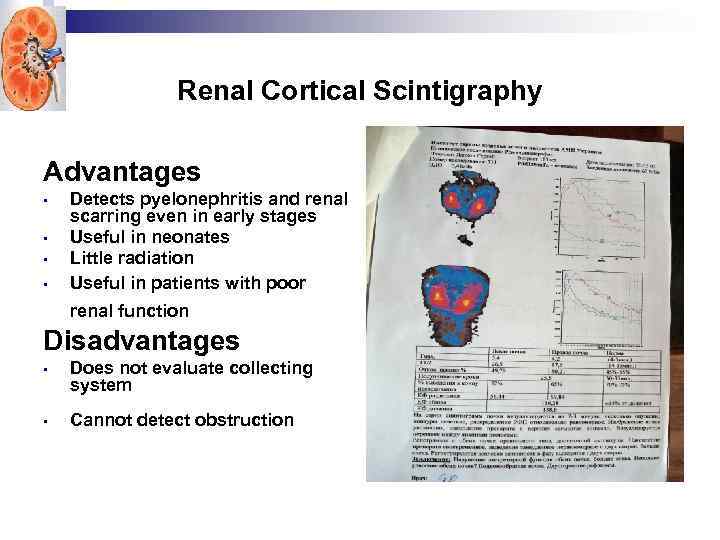

Renal Cortical Scintigraphy Advantages • • Detects pyelonephritis and renal scarring even in early stages Useful in neonates Little radiation Useful in patients with poor renal function Disadvantages • Does not evaluate collecting system • Cannot detect obstruction

Renal Cortical Scintigraphy Advantages • • Detects pyelonephritis and renal scarring even in early stages Useful in neonates Little radiation Useful in patients with poor renal function Disadvantages • Does not evaluate collecting system • Cannot detect obstruction